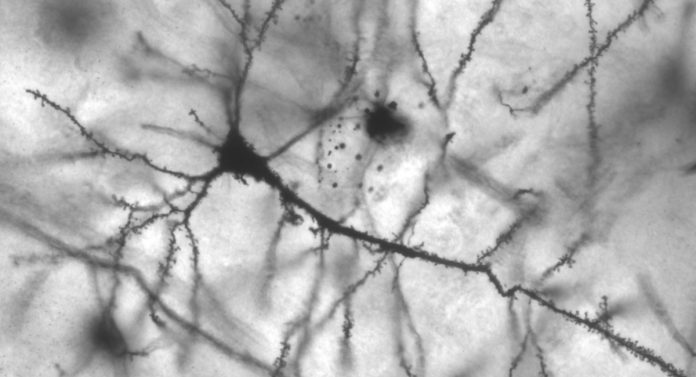

Miguel Ribeiroe colleghi hanno ipotizzato che i linfociti T gamma-delta produttori di IL-17 potessero svolgere un ruolo anche sull’attività cognitiva in uno stato non infiammatorio e quindi fisiologico. Per dimostrarlo hanno sottoposto alcuni topi ad un trattamento con anticorpi monoclonali che rimuovevano in maniera selettiva la proteina IL-17, dopodiché hanno messo alla prova le loro capacità cognitive e di memoria. Effettivamente, come ipotizzato, i topolini carenti di IL-17 presentavano una forte compromissione della memoria a breve termine e un ridotto potenziamento a lungo termine, importante indice di plasticità sinaptica, rispetto ai topi di controllo. Inoltre, coltivando delle cellule gliali arricchite di IL-17, i ricercatori hanno notato un incremento significativo nella produzione del fattore neurotrofico cerebrale (BDNF). Somministrando IL-17 quindi è stato possibile ripristinare le attività cognitive e mnemoniche dei topolini.